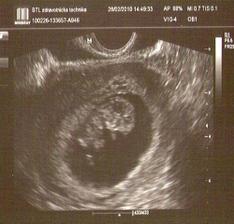

25. září čekáme miminko

Po jednou neúspěchu teď věříme v úspěch. Držte palce!